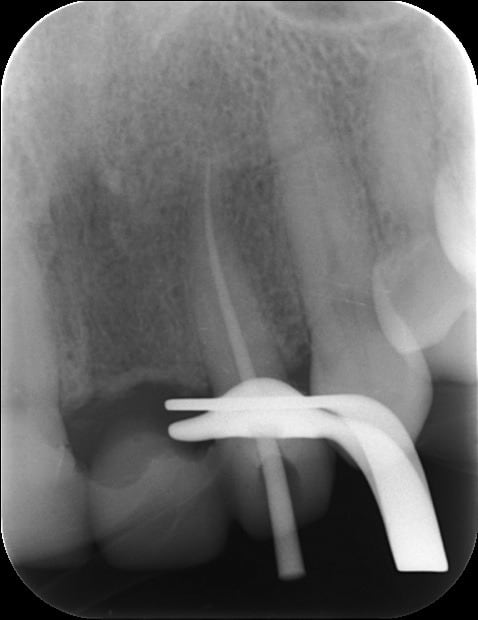

10/07/2012 à 23h01

Je déterre mon poste en mettant les photos du cas. Désolé il manque le principal: la photo de l'état initial...

Donc par précaution, j'ai choisi de faire l'endo sur la 22, suite au coiffage direct (même si la dent était asymptotique pour la patiente).

Je n'ai pas osé faire que de l'Emax. J'ai décidé avec le labo de faire une armature Zircone avec de l'Emax pressée dessus.

Il y a les photos du biscuit, du bridge fini le jour de la pose et à 3 semaines.

A vos critiques, merci!

10/07/2012 à 23h39

C'est très beau.

Et belle endo aussi :-)